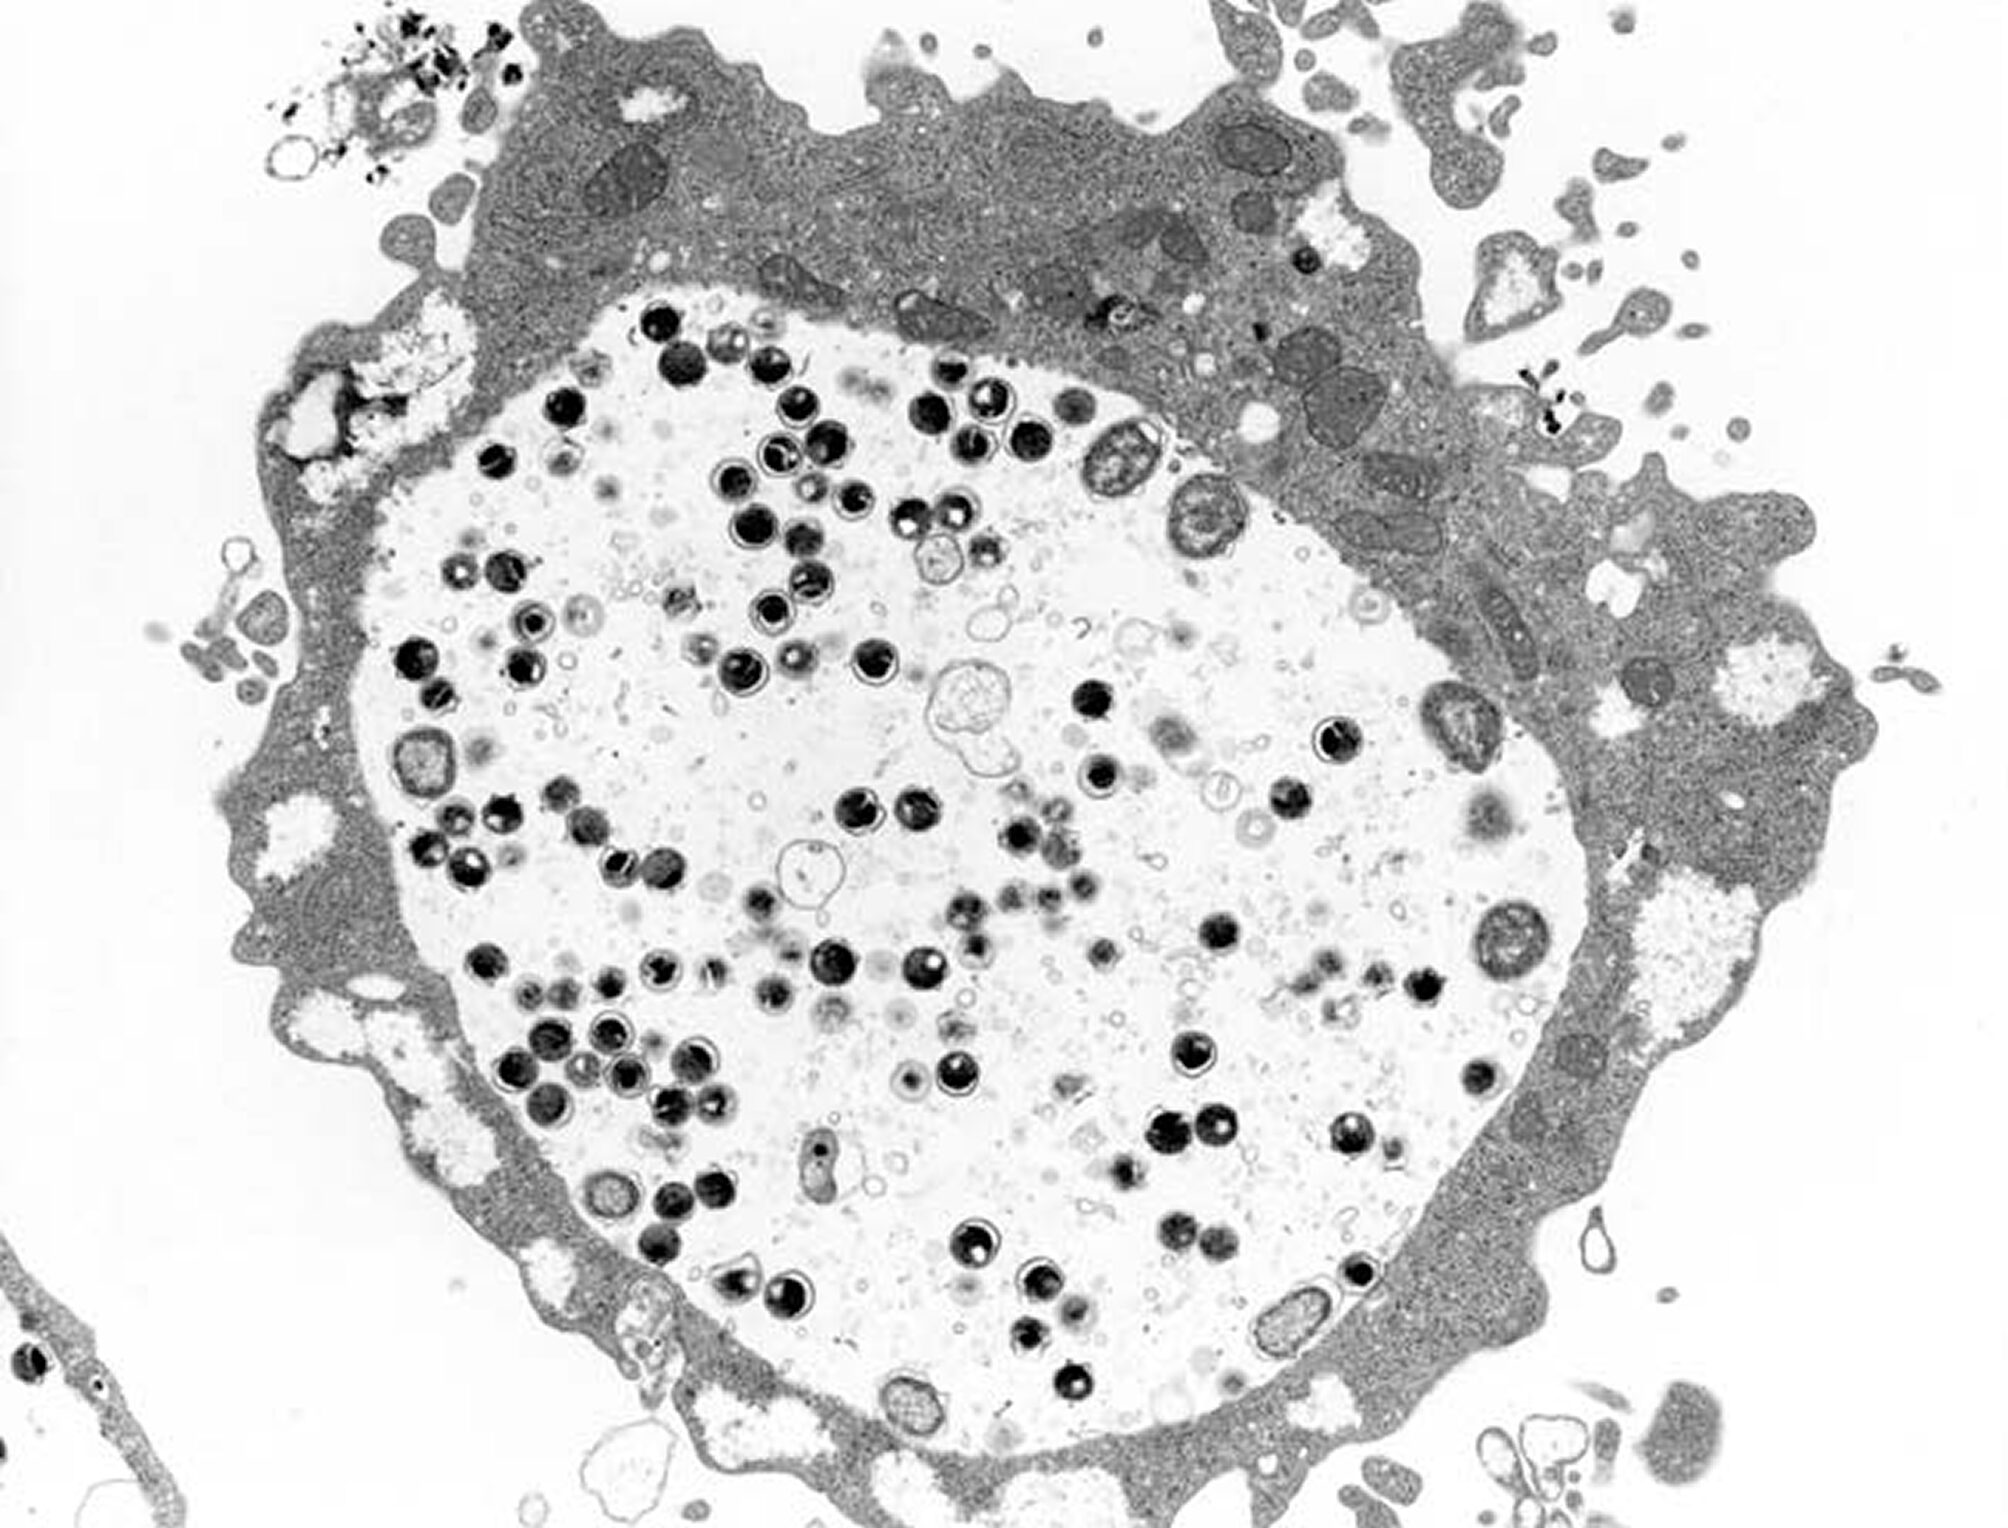

腟トリコモナス症

腟トリコモナス原虫が原因で起こる感染症で、性行為が主な感染経路です。

| 潜伏期間 | 5~28日程度 |

|---|---|

| 症状 |

・おりものの異常 (増加、泡状、黄緑色、強い悪臭) ・外陰部の強い痒み ・性交時の痛み |

原虫が原因のため、性行為以外にもタオル、便器、浴槽などを共有することで感染するケースがあります。そのため、性行為の経験がない方や幼児にも感染することがあります。

女性の場合、トリコモナス感染による腟炎を起こすと上記のような症状が出ます。男性のトリコモナス感染はほとんど症状が現れませんが、女性は比較的症状を感じやすいです。ただし、20~50%の方が無症状ともいわれているため注意が必要です。

トリコモナスも他の性感染症と同様、放置するとパートナーに感染させてしまうだけでなく、不妊症や早産、流産のリスクが高まります。早期発見・早期治療が大切です。